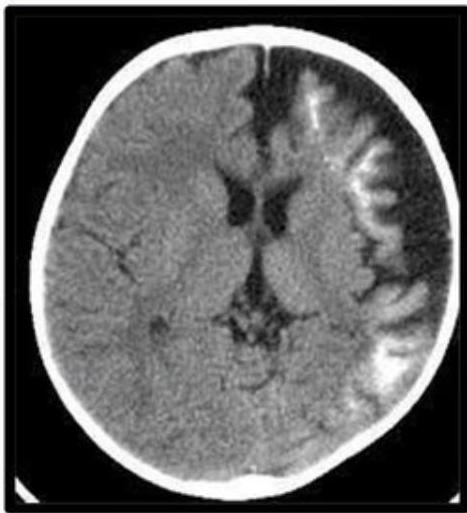

- Brain Atrophy & Calcification: Underlying brain becomes atrophic and calcified (“Tram track” calcification).

- Skull X-ray/CT: Shows Tram track calcification (gyriform calcification).